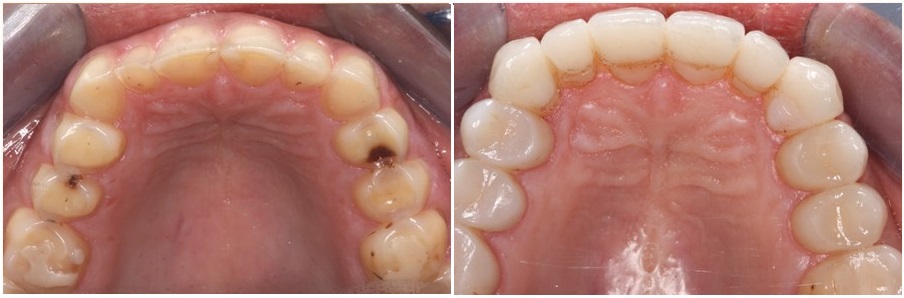

The following pictures present the occlusal surfaces of the maxillary and mandibuler teeth, before and after the cementation of our aditive restorations.

Most teeth had lost their enamel and a significant portion of dentin. Teeth had also lost their anatomical features while the height of the lower third of her face had decreased.

Old fillings were protruding over her teeth, ans some of the teeth were decayed.

Erosion had affected most of the maxillary and mandibular teeth.